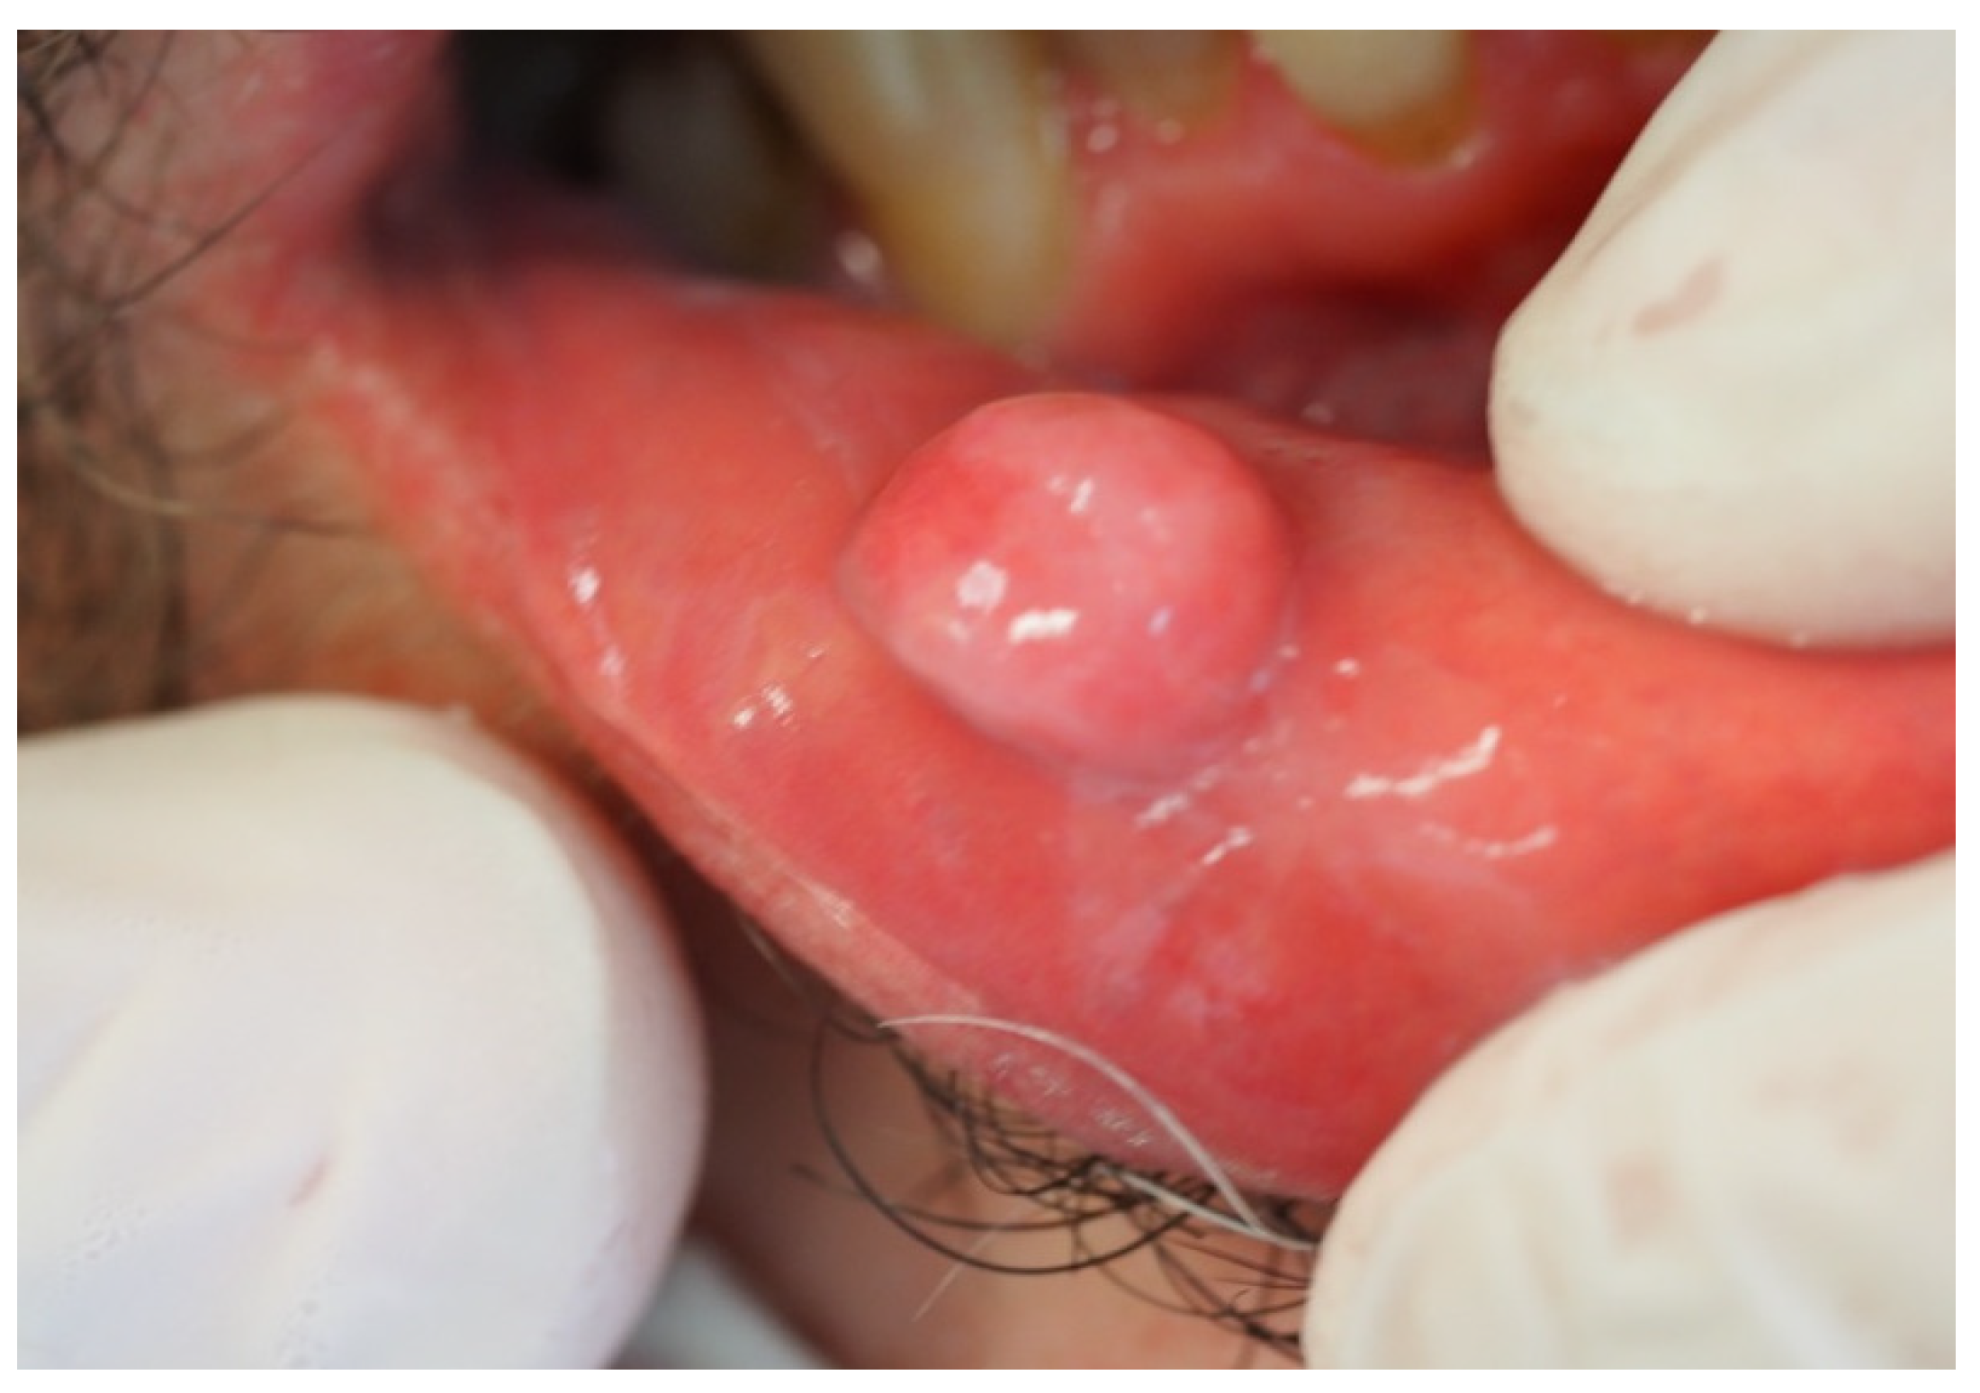

| Mucocele | 105 | 3.8 | 36.0 | 51 | 2.8 | 39.0 | 54 | 5.9 | 30.0 |